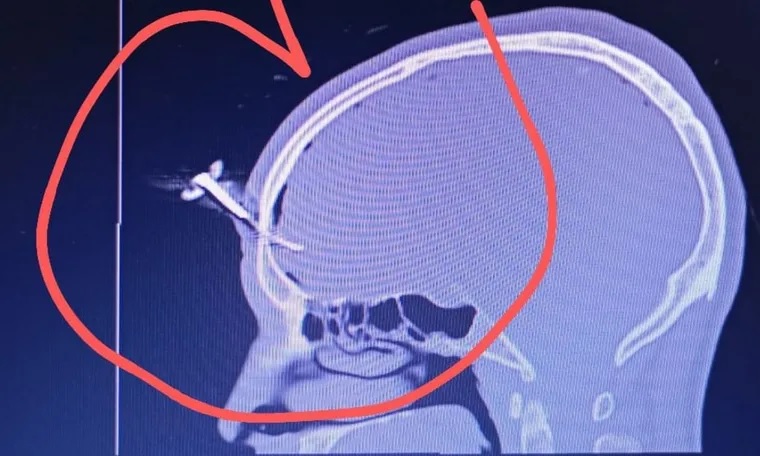

Le clavaron una llave en la cabeza durante una feroz pelea

Una violenta pelea entre padres durante un partido juvenil en el Club Gimnasia y Esgrima de Villa España (GEVE), en Berazategui, terminó con un exfutbolista gravemente herido. A Jonathan José “El Corto” Smith, de 35 años, exjugador de la Asociación Deportiva Berazategui (ADB), le clavaron una llave de auto en la cabeza y se encuentra internado en terapia intensiva.

El episodio ocurrió en la noche del miércoles, durante un campeonato femenino Sub 16. Según testigos, Smith habría intervenido para defender a un amigo al que estaban golpeando, cuando uno de los involucrados lo atacó con una llave de vehículo, que se incrustó en su frente.

Así quedó la víctima del ataque con una llave

En redes sociales circularon imágenes sensibles donde se muestra el rostro del exfutbolista con la llave incrustada en su rostro ensangrentado. Según se conoció, el hombre en ningún momento perdió la consciencia. MDZ